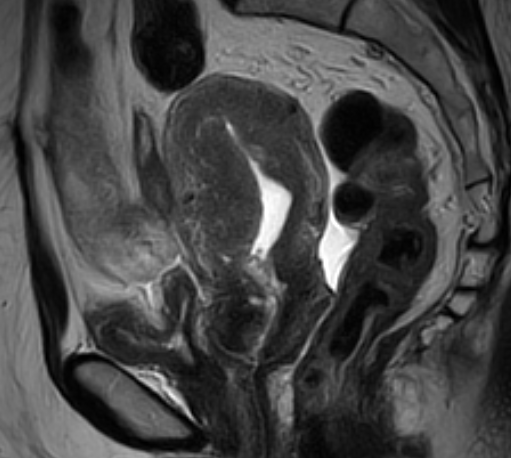

盆腔增强核磁:

1.考虑子宫内膜占位性病变,请结合病理检查;

2.宫颈多发小囊肿;

3.宫腔少量积液;

4.盆腔积液。